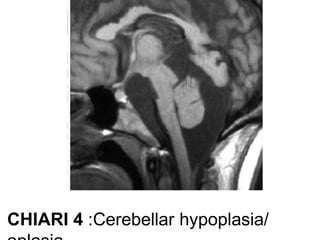

• Chiari type IV

hypoplasia / aplasia of cerebellum with no hindbrain herniation

IV• cerebellar hypoplasia or aplasia(1896).

Post fossasizenormal.

• No hindbrain herniation.

• Tentorium cerebelli also

hypoplastic.

CHIARI 4 :Cerebellar hypoplasia/